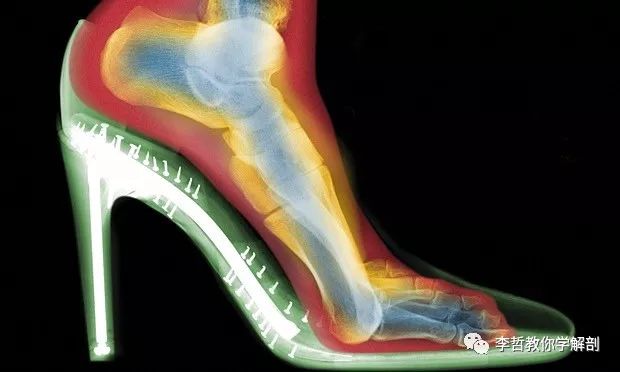

大部分拇外翻是由穿着窄身,尖头或高跟鞋引起。经常穿着这种鞋,将拇指向外推,这牵拉到位于拇指内侧的肌肉(拇外展肌),令他失去了弹性。

患者也可以穿着矮跟约1.3厘米的鞋。流行病学的研究发现,16岁时,超过五成的少女都已经穿着高跟鞋。相对于赤足穿着2厘米高的鞋时,前掌的压力比赤足高22%。穿着5厘米高的鞋时,前掌的压力相对高57%。而穿着8厘米以上的鞋时,前脚掌的压力高于赤足76%。